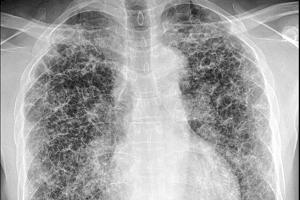

При поражении легких может отмечаться кашель, одышка, повышение температуры, слабость и похудение.

Этот вид гистиоцитоза является не опухолевым, а реактивным процессом. В этом случае заболевшие клетки остаются нормальными и есть вероятность, что они поправятся сами. Чаще всего он развивается в ответ на воздействие на легкие (курение!) у предрасположенных людей. Появляется сухой кашель, одышка, а при компьютерной томографии вместо нежной губчатой ткани легких доктор видит участки без легочной ткани – буллы.

Рисунок 1. Нормальная КТ-картина легких Рисунок 2. Легочные КТ-изменения у пациента с гистиоцитозом